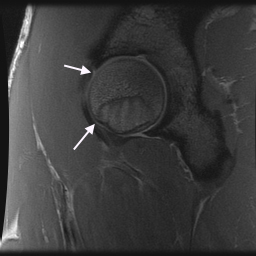

21 year old male with hip pain. Mild FAI on arthrogram with small bump and small anterior labral tear. Also, an accesory ligamentum plica although they can be symtomatic. In figure 3 the long arrow points to the true ligamentum, the short to the accessory ligamentum. In figures 1 and 4 the accessory is shown.

Hip Plica